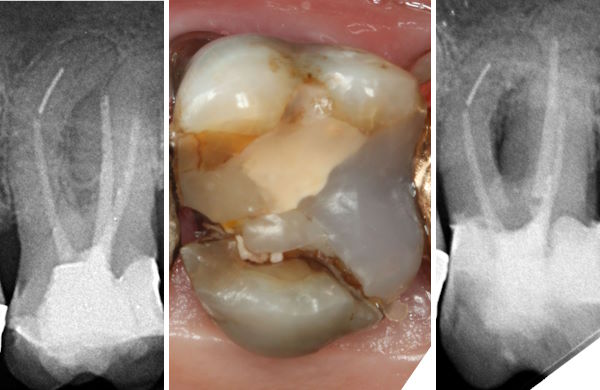

Anamnese:

29.09.2000: 2-flächige Kompositfüllung (MO)

03.07.2012: 2-flächige Kompositfüllung (OD) mit direkter Überkappung Grad 2

09.01.2013: PE nach Notfallbehandlung

02.04.2014: WF 4 Kanäle

02.07.2014: kleine 1-flächige Füllung am Zahnhals

01.12.2014: Kauschmerzen wegen Fraktur der Füllung

links: Zentralfraktur im Cavumboden

rechts: Bruchspalt erweitert

links: Bruchspalt verschlossen und Löcher für die Drahtverstärkung

rechts: Füllung fertig, durchschimmernde Drahtverstärkung